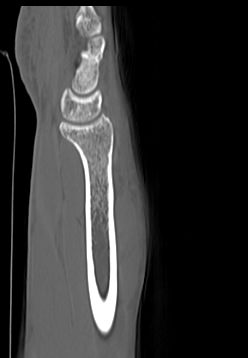

Кроме того, компьютерная томография проводится при планировании оперативного вмешательства и в послеоперационном периоде для визуального контроля успешности проведенной операции, мониторинга процесса восстановления костных тканей.

Мультиспиральная КТ одного сустава наиболее часто применяется в ортопедии, травматологии, хирургии, онкологии и ревматологии. Данное исследование позволяет диагностировать:

- Травматические повреждения костей скелета (различные переломы, ушибы надкостницы, вывихи, разрывы связок);